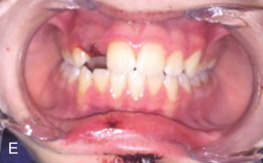

Next, each remaining tooth and restoration should be evaluated systematically (see Classification section ). Transillumination of visible light along the long axis of the tooth can identify subtle dental injuries to enamel. Each tooth should be evaluated for mobility, both individually or along with its adjacent teeth (indicating a dentoalveolar fracture). Mobility of an individual tooth can indicate luxation of the entire tooth or a root fracture that can require dental radiographs to diagnose. The clinician should then evaluate the alignment of the dental arches. Teeth are most commonly displaced in a buccolingual direction due to the vector of trauma perpendicular to the tooth’s long axis. A tilting of the occlusal plane can indicate luxation or intrusion injuries, but may indicate maxillary or mandibular fracture. Each tooth should be tested for mobility in all dimensions with care not to avulse loose teeth or dentoalveolar segments. A commonly used mobility index is the Miller classification, in which tooth mobility is evaluated using two hard objects (e.g. two tongue depressors). If a tooth is nondisplaced but mobile, this may indicate either preexisting periodontal disease or a crown/root fracture. Dental fractures more coronally positioned generally have more mobility.

Intraoral occlusal exam: The patient is instructed to carefully bring their teeth into occlusion with the clinician evaluating the movement. Premature occlusal contacts could indicate fracture or luxation injuries. The patient is then guided into their premorbid occlusion if tolerated. This allows the clinician to determine the complexity of restoring the patient’s dentition. Interferences of the palatal cusps of the molars with a seemingly intact mandible could indicate a palatal fracture with change in the transverse width of the maxilla.